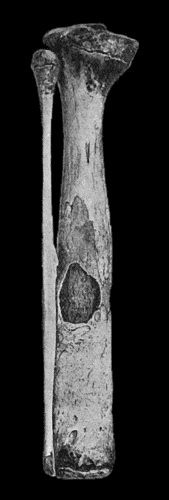

445 120.Segment of Tibia resected for Brodie's Abscess

449 121.Radiogram of Brodie's Abscess in Lower End of Tibia